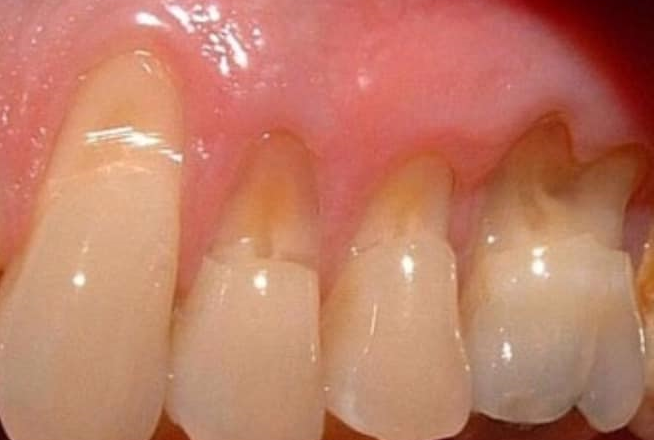

MÒN CỔ RĂNG - BIỆN PHÁP PHÒNG NGỪA VÀ XỬ TRÍ

29/05/2024 (GMT+7)

Trong quá trình thăm khám bệnh tại Khoa Răng Miệng - Bệnh viện Đa khoa tỉnh Hải Dương, chúng tôi gặp một bệnh rất phổ biến, nhiều bệnh nhân mắc phải và đã được chúng tôi xử lý rất nhiều đó là: mòn cổ răng.